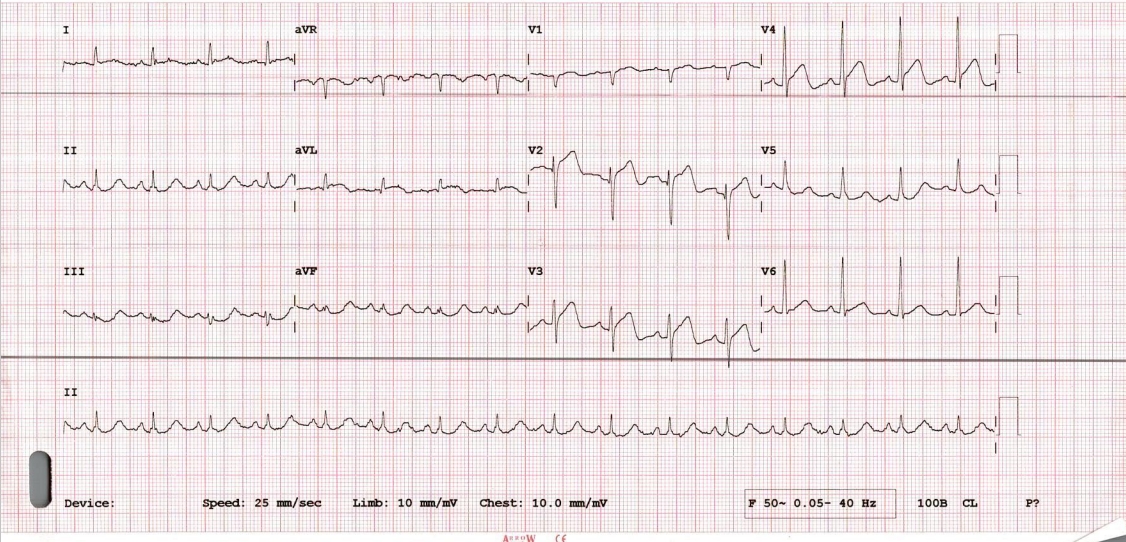

His baseline ECG showed ST elevation in V1-V4 . Echocardiography revealed Hypokinesia of anterior wall and LV ejection fraction of 40%.His initial blood sugar was 352 mg/dl ,serum creatinine of 1.45 mg/dl and Troponin I was 8096 ng/L . Patient was immediately taken for primary angioplasty.